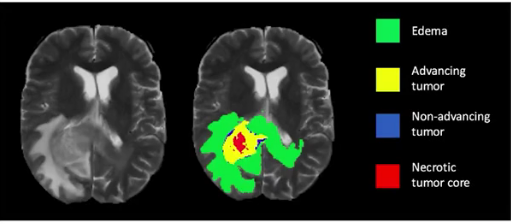

图像分割是一种根据存在的对象及其语义重要性对图像进行划分的像素级分类预测任务,其致力于为图像中的每一个目标都生成一个像素级别的掩膜,也就是大家耳熟能详的——mask。

对于计算机视觉领域来说,图像分割指的是将数字图像细分为多个图像子区域或称为超像素的过程。图像分割的目的是简化或改变图像的表示形式,使得图像更容易理解和分析。图像分割通常用于定位图像中的物体和边界(线,曲线等),是对图像中的每个像素加标签的一个过程,这一过程使得具有相同标签的像素具有某种共同视觉特性。

或许很多人心中都有一个疑问,那便是我们是否需要如此精心的预测一张图像中的目标?其实,对于绝大数CV应用场景来说,仅依赖目标检测是可以解决的。但是,这并不意味图像分割就没有存在的意义。举个简单的例子,比如癌症,大家都知道这个都是由癌细胞扩散所造成的。通常,癌细胞的形状在确定癌症的严重程度中起着至关重要的作用,这时候图像分割便派上用场了。